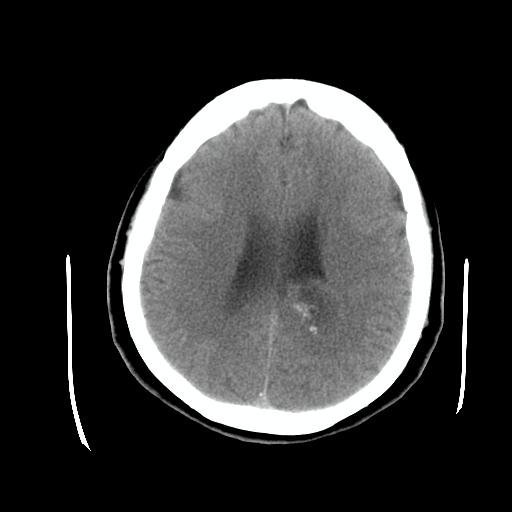

标题: CT24768:双侧脑室内囊性病变,主各位站友会诊。 [打印本页]

标题: CT24768:双侧脑室内囊性病变,主各位站友会诊。

患者女,62岁,临床提供头痛、头晕数月,无恶心及呕吐,近日加重。请各位站友看看,能否定为双侧脑室脉络丛囊肿,如果不能,应考虑什么?谢谢!

室管膜钙化 脑内多发钙化灶 可考虑寄生虫 结核等颅内感染

首选考虑---脑囊虫病。

脉络丛囊肿属神经上皮性囊肿.好发于双侧脉络膜球,通常于影像检查或活检时偶然发现.患者无症状,病灶较小,双侧对称性,脑室膨胀轻.多数病灶在信号上与室管膜囊肿有所不同.在dwi上呈部分高信号,t2 flair上呈不均匀高信号.增强后呈结节状或环形增强

除了脉络膜丛囊肿外,枕叶内的片状钙化密度影,其周围无水肿,可能还要考虑血管畸形吧,建议增强扫描以明确诊断。